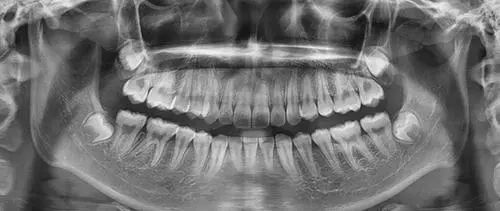

五、为什么根管治疗需要拍多张牙片

根管治疗时,拍牙片是很有必要的,并且至少要保证3张牙片。

第一张在治疗前,帮助医生了解牙根的基本情况,制定治疗计划;

第二张在治疗中,帮助医生了解治疗情况,如根管预备是否到位等,并制定下一步治疗方案;

第三张是在治疗结束后,帮助判定根管充填质量,发现问题及时补救。